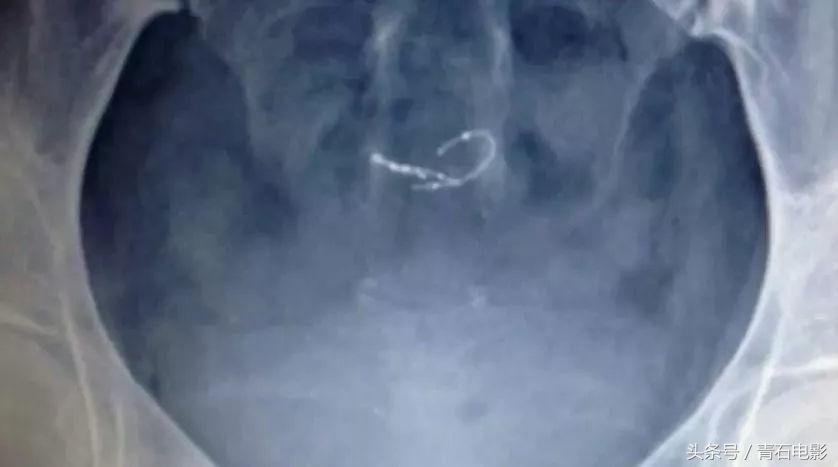

Essure由一个微小的四公分线圈组成,通过子宫插入并放置在输卵管内。

网飞出品的纪录片,上映后让美公司停售一款尖端医疗器械!

它的工作原理是:刻意造成输卵管的发炎反应,以形成结痂组织。

然后结痂组织会永久性的关闭输卵管。

结果发现:Essure已经由输卵管跑到了子宫里。